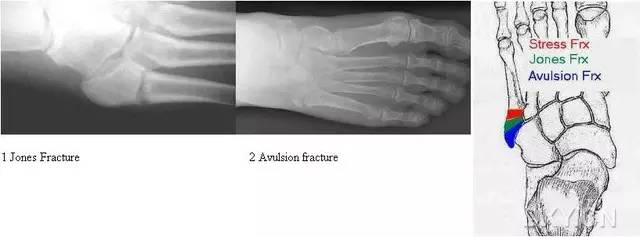

14.第五跖骨骨折

第五跖骨基底部骨折的不同类型:Stress 骨折;Jones 骨折:第五跖骨基底部以远 1 英寸内的骨折称为 Jones 骨折;Avulsion 骨折。

(来源:Radiopaedia)

Stress 骨折(来源:OrthoInfo-AAOS)

Jones 骨折正位片(来源:Radiopaedia)

Jones 骨折斜位片(来源:Radiopaedia)